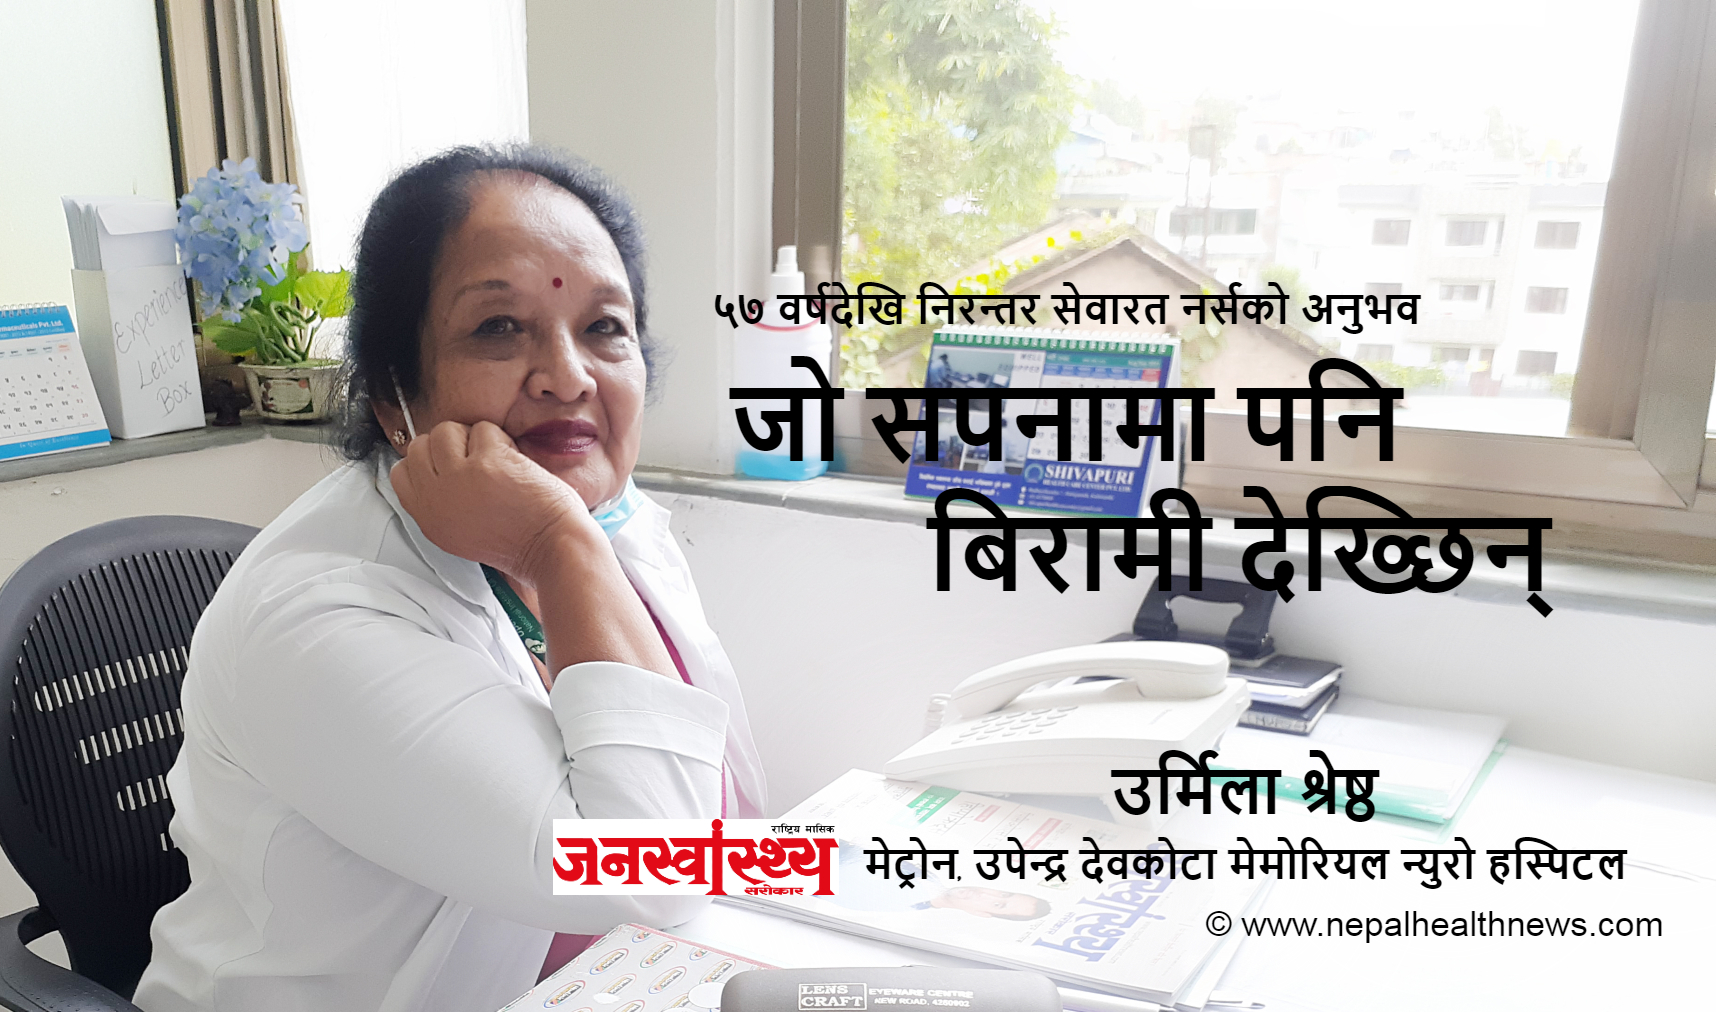

‘जो सपनामा पनि बिरामी देख्छिन्’

शुक्रबार, असोज १५, २०७८

सन् १९६१ को त्यो डिसेम्वरलाई सम्झदा...

शुक्रबार, असोज १५, २०७८